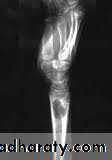

X-Ray

Typically shows small oval radiolucent area surrounding by sclerotic bone (the classical brodies abscess).